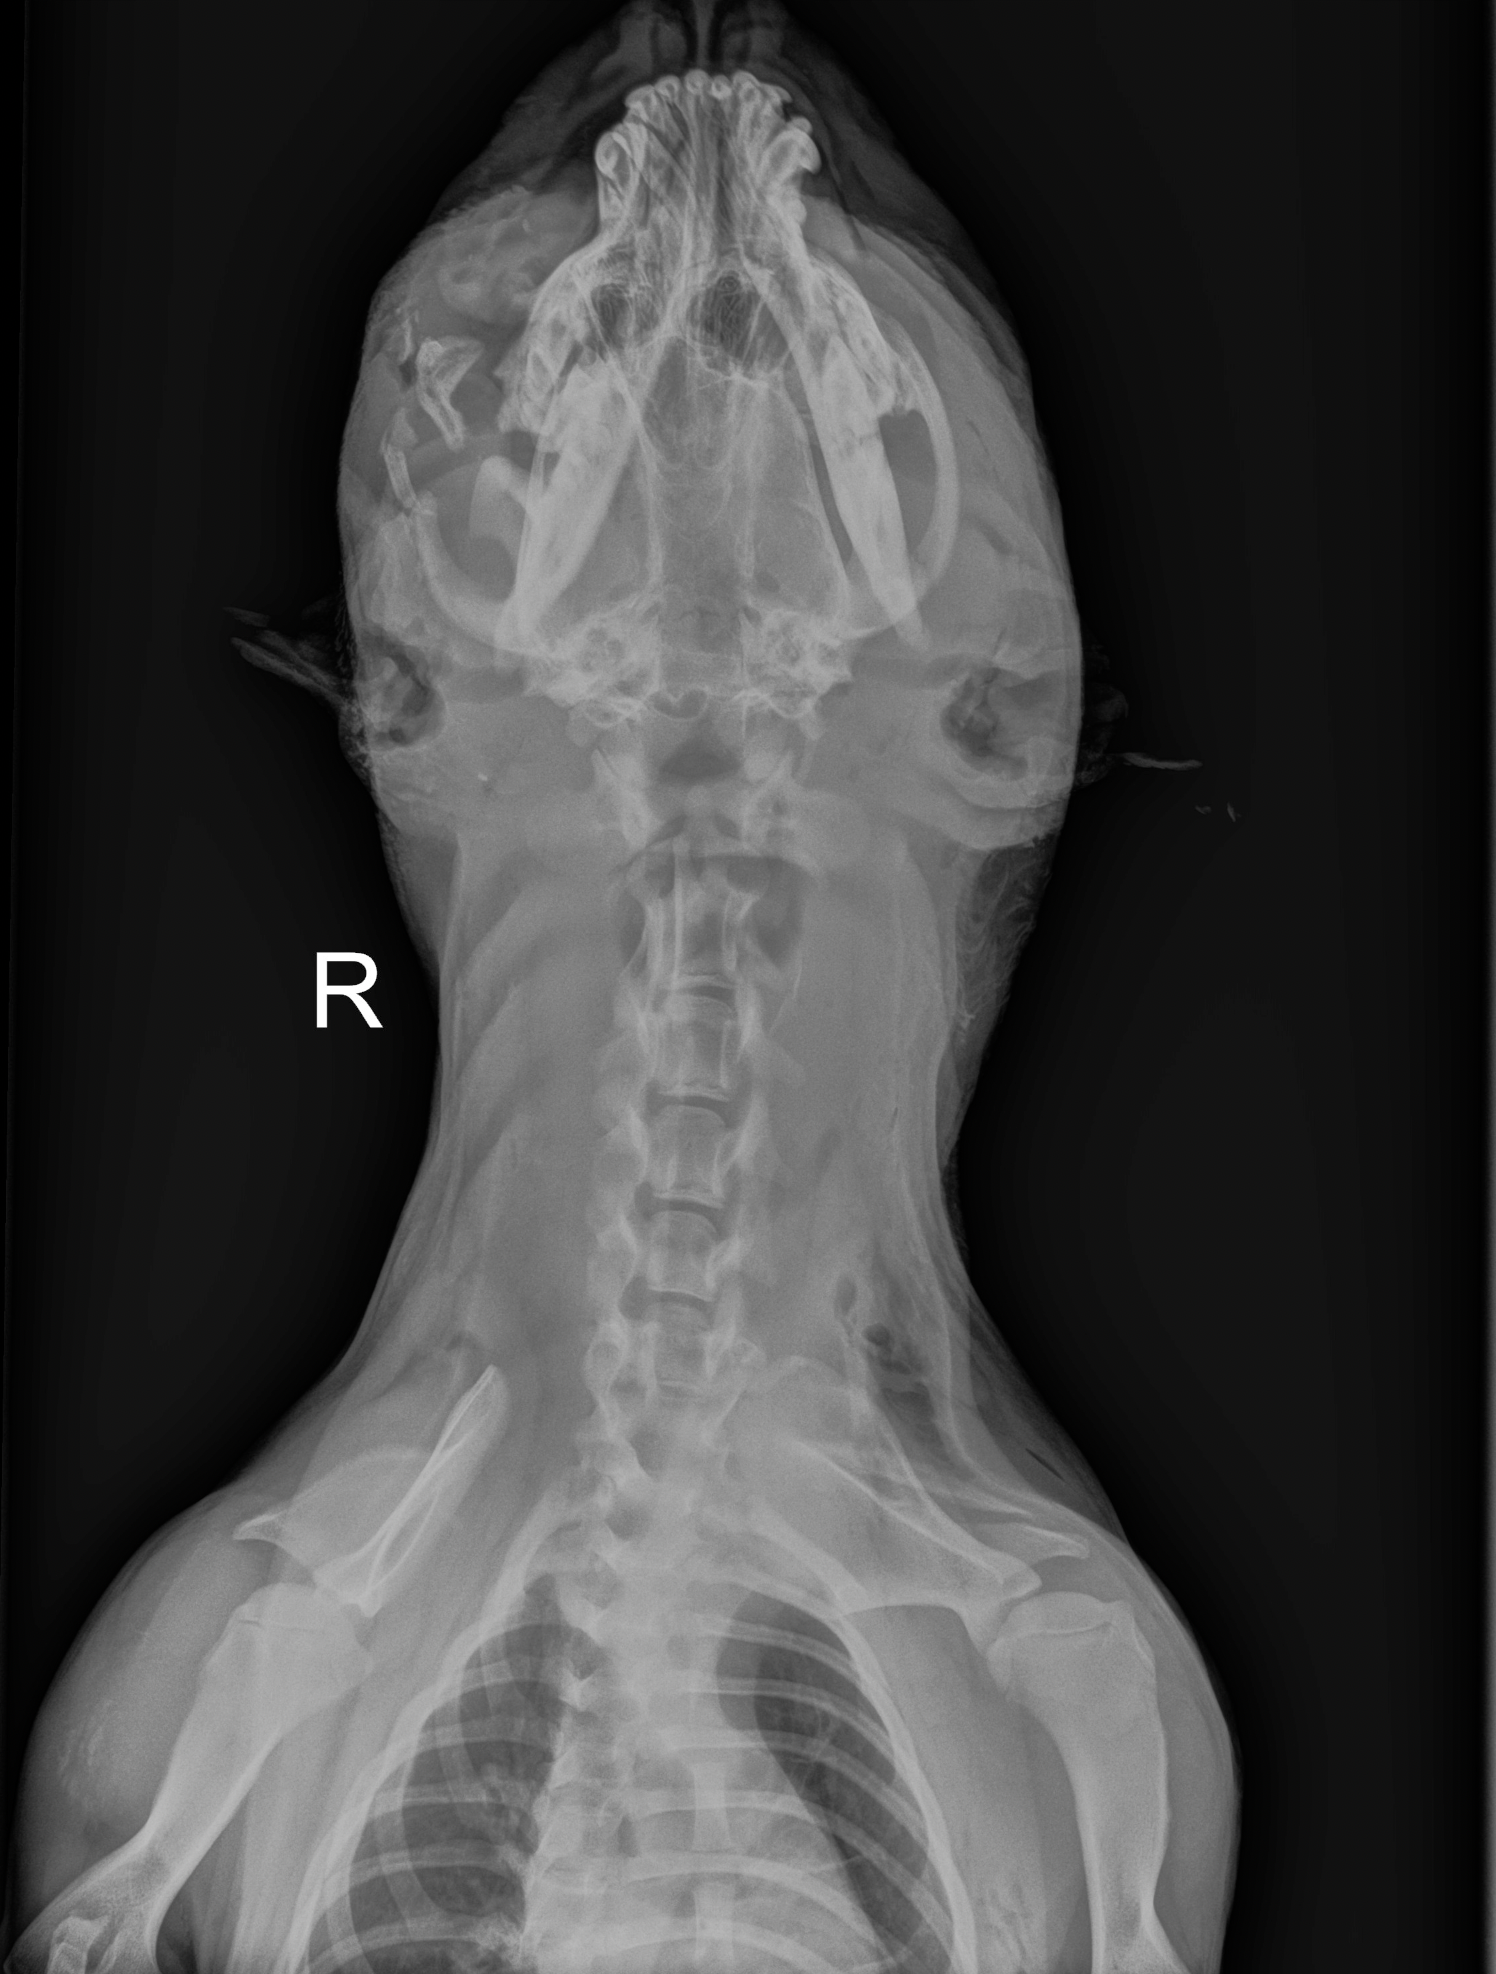

Once Jessie was sedated and her wounds were cleaned, the true extent of her trauma was revealed through the cold, gray lens of an X-ray.

The findings were shocking. The orbital bone—the structure right below her eye—was completely shattered. Her teeth on the same side were a mess of broken enamel and roots. While the majority of the trauma was concentrated on one side of her face, wounds were also found hidden behind her ears and on top of her head.

It remained a mystery. There were no bullet holes, and while they looked like bite wounds, there wasn’t a single scratch on her legs or body. It was as if someone—or something—had targeted only her head. Despite the low blood cell counts and the severe infection, her doctors remained focused. Jessie was finally in the right hands.